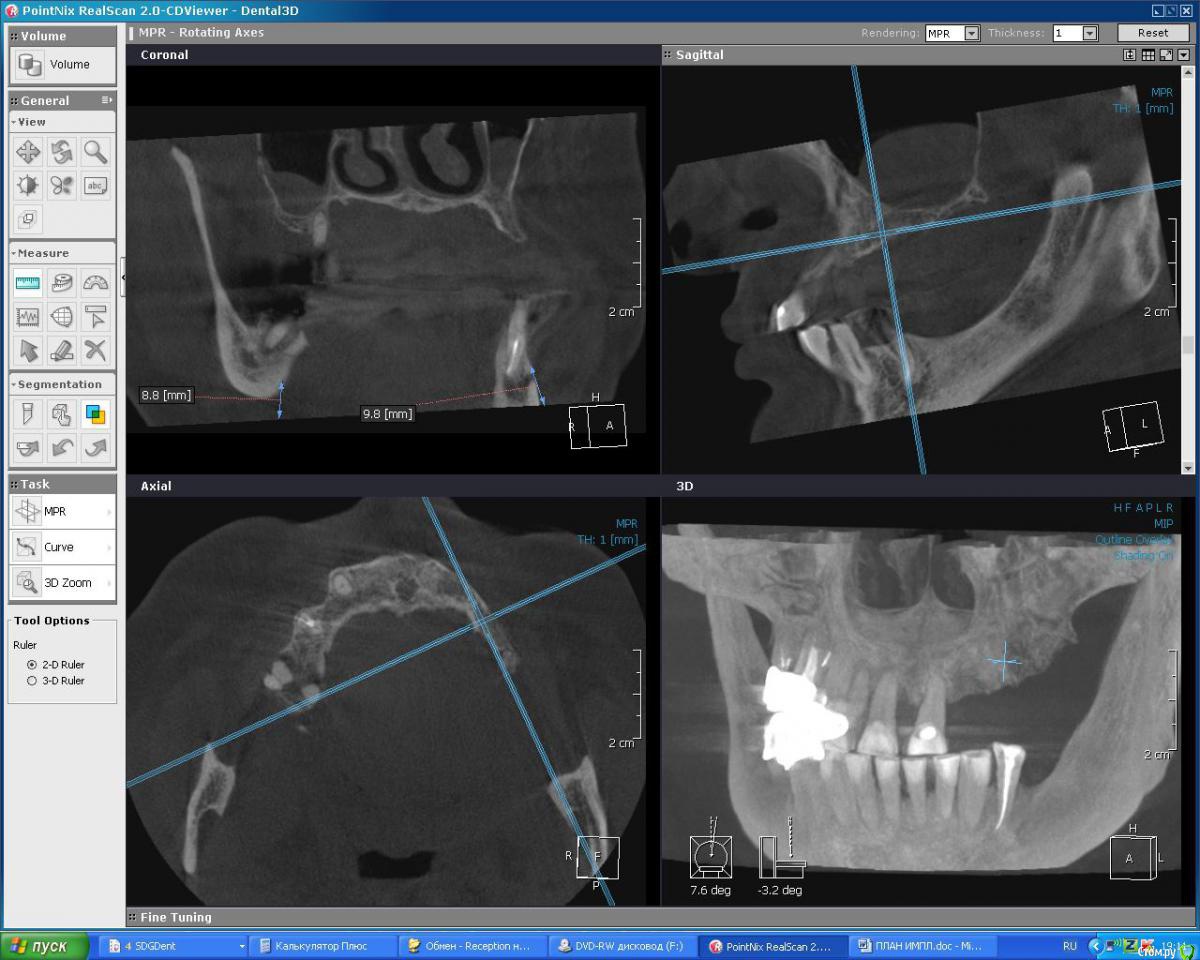

DoktorDre Опубликовано 23 декабря, 2015 Поделиться Опубликовано 23 декабря, 2015 Добрый вечер, коллеги. Хотим импланты, анализ моделей, кт показал что не хватает кости Небно. По высоте почти норм. Как вырастить там кость? Небный лоскут не тянется. Делать дизайн лоскута с щечной стророны? Ссылка на комментарий